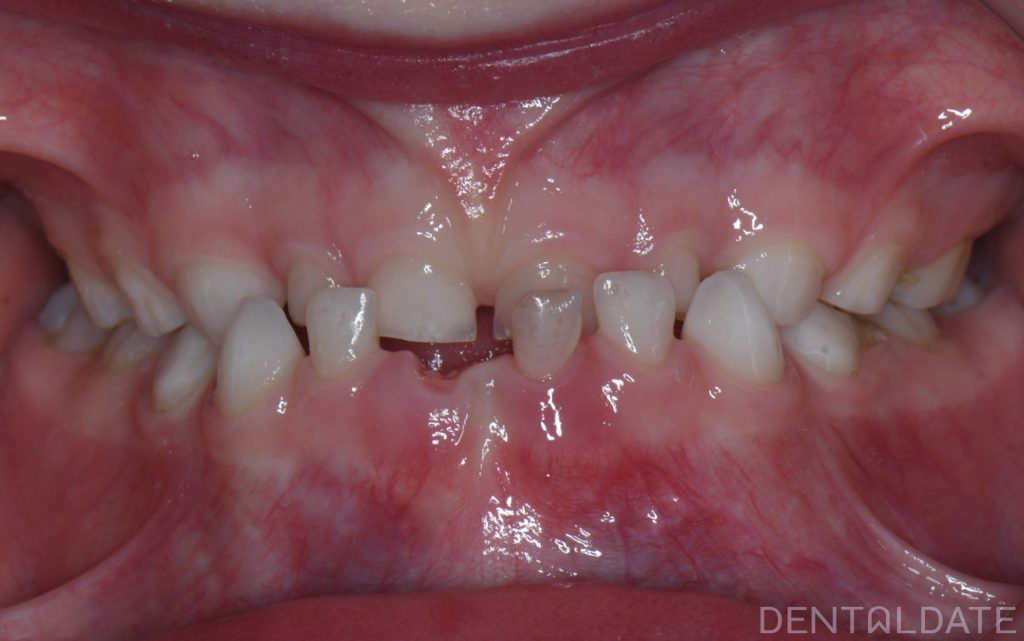

The patient’s mother came in for a consultation, reporting that her child was experiencing difficulty chewing and rarely smiled.

A key goal of children orthodontic treatment is to normalize physiological growth and development.